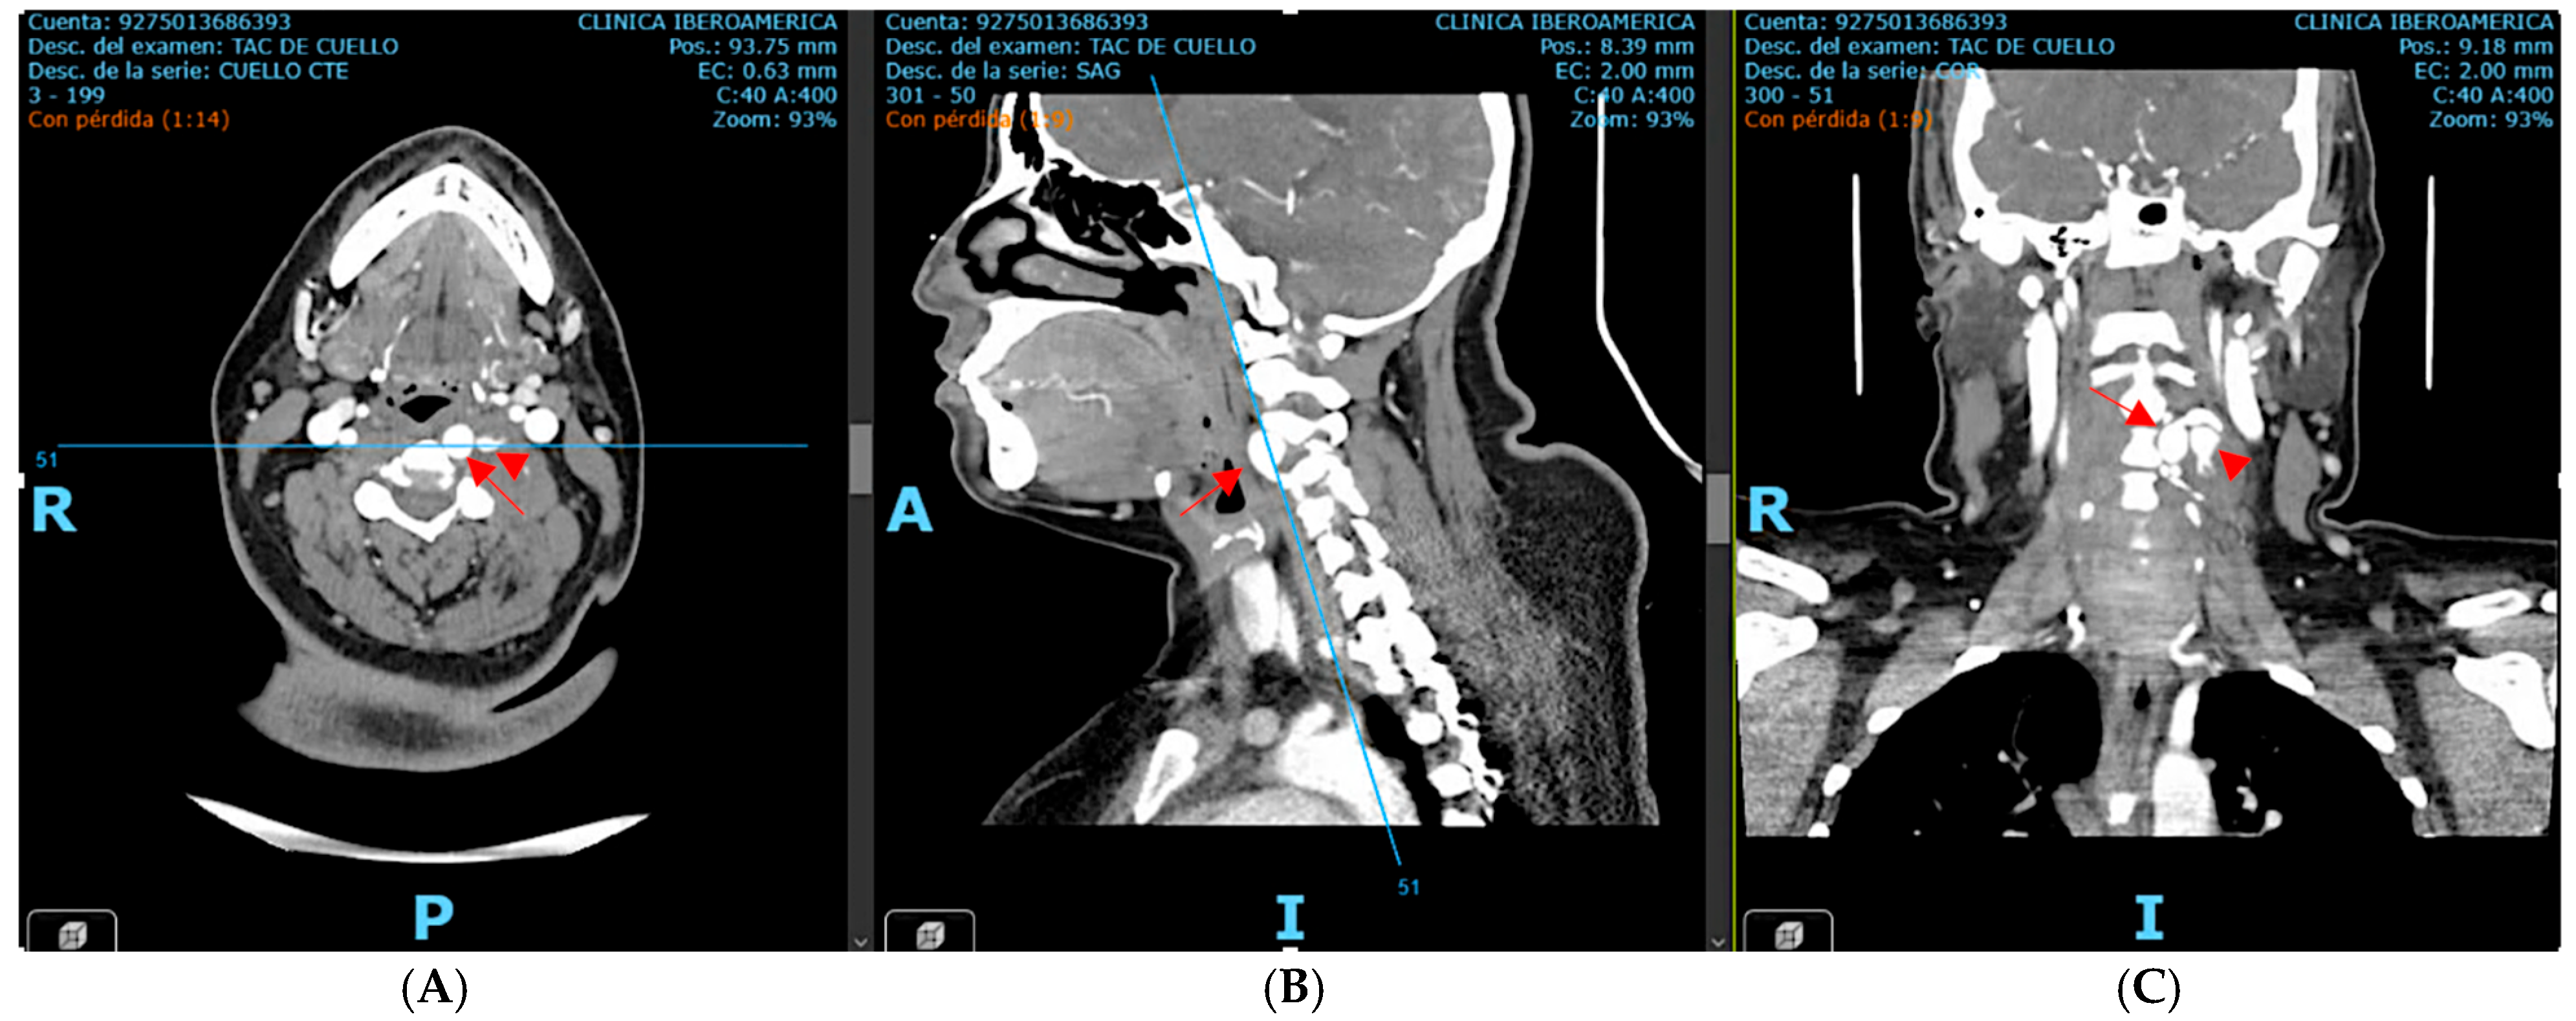

Subsequent computed tomography angiography (CTA) of the neck and cerebral vessels demonstrated a tortuous left vertebral artery with a fusiform aneurysm in the V2 segment measuring 10 × 14 mm, with an associated mural defect and active contrast extravasation into a perivertebral collection of 34 × 24 mm (Figure 2).

Figure 2. Contrast-enhanced CT angiography of the neck and cerebral vessels, axial view (A), sagittal view (B), and coronal view (C), performed after intravenous administration of 100 mL of non-ionic iodinated contrast medium (Iohexol, Omnipaque® 300 mg I/mL, injection rate 3–4 mL/s). Image acquisition was performed during the arterial phase using a bolus-tracking technique (approximately 20–25 s after injection, triggered when the contrast density in the aortic arch reached ≥120 Hounsfield units). The study demonstrates a tortuous left vertebral artery with fusiform aneurysmal dilation of the V2 segment, measuring approximately 10 × 14 mm. A focal mural defect is identified, with active contrast extravasation into a contained perivertebral hypodense collection (34 × 24 mm). The aneurysmal dilation is marked by the red arrow, while the mural defect is indicated by the arrowhead. Source: patient’s medical record, published with prior authorization.